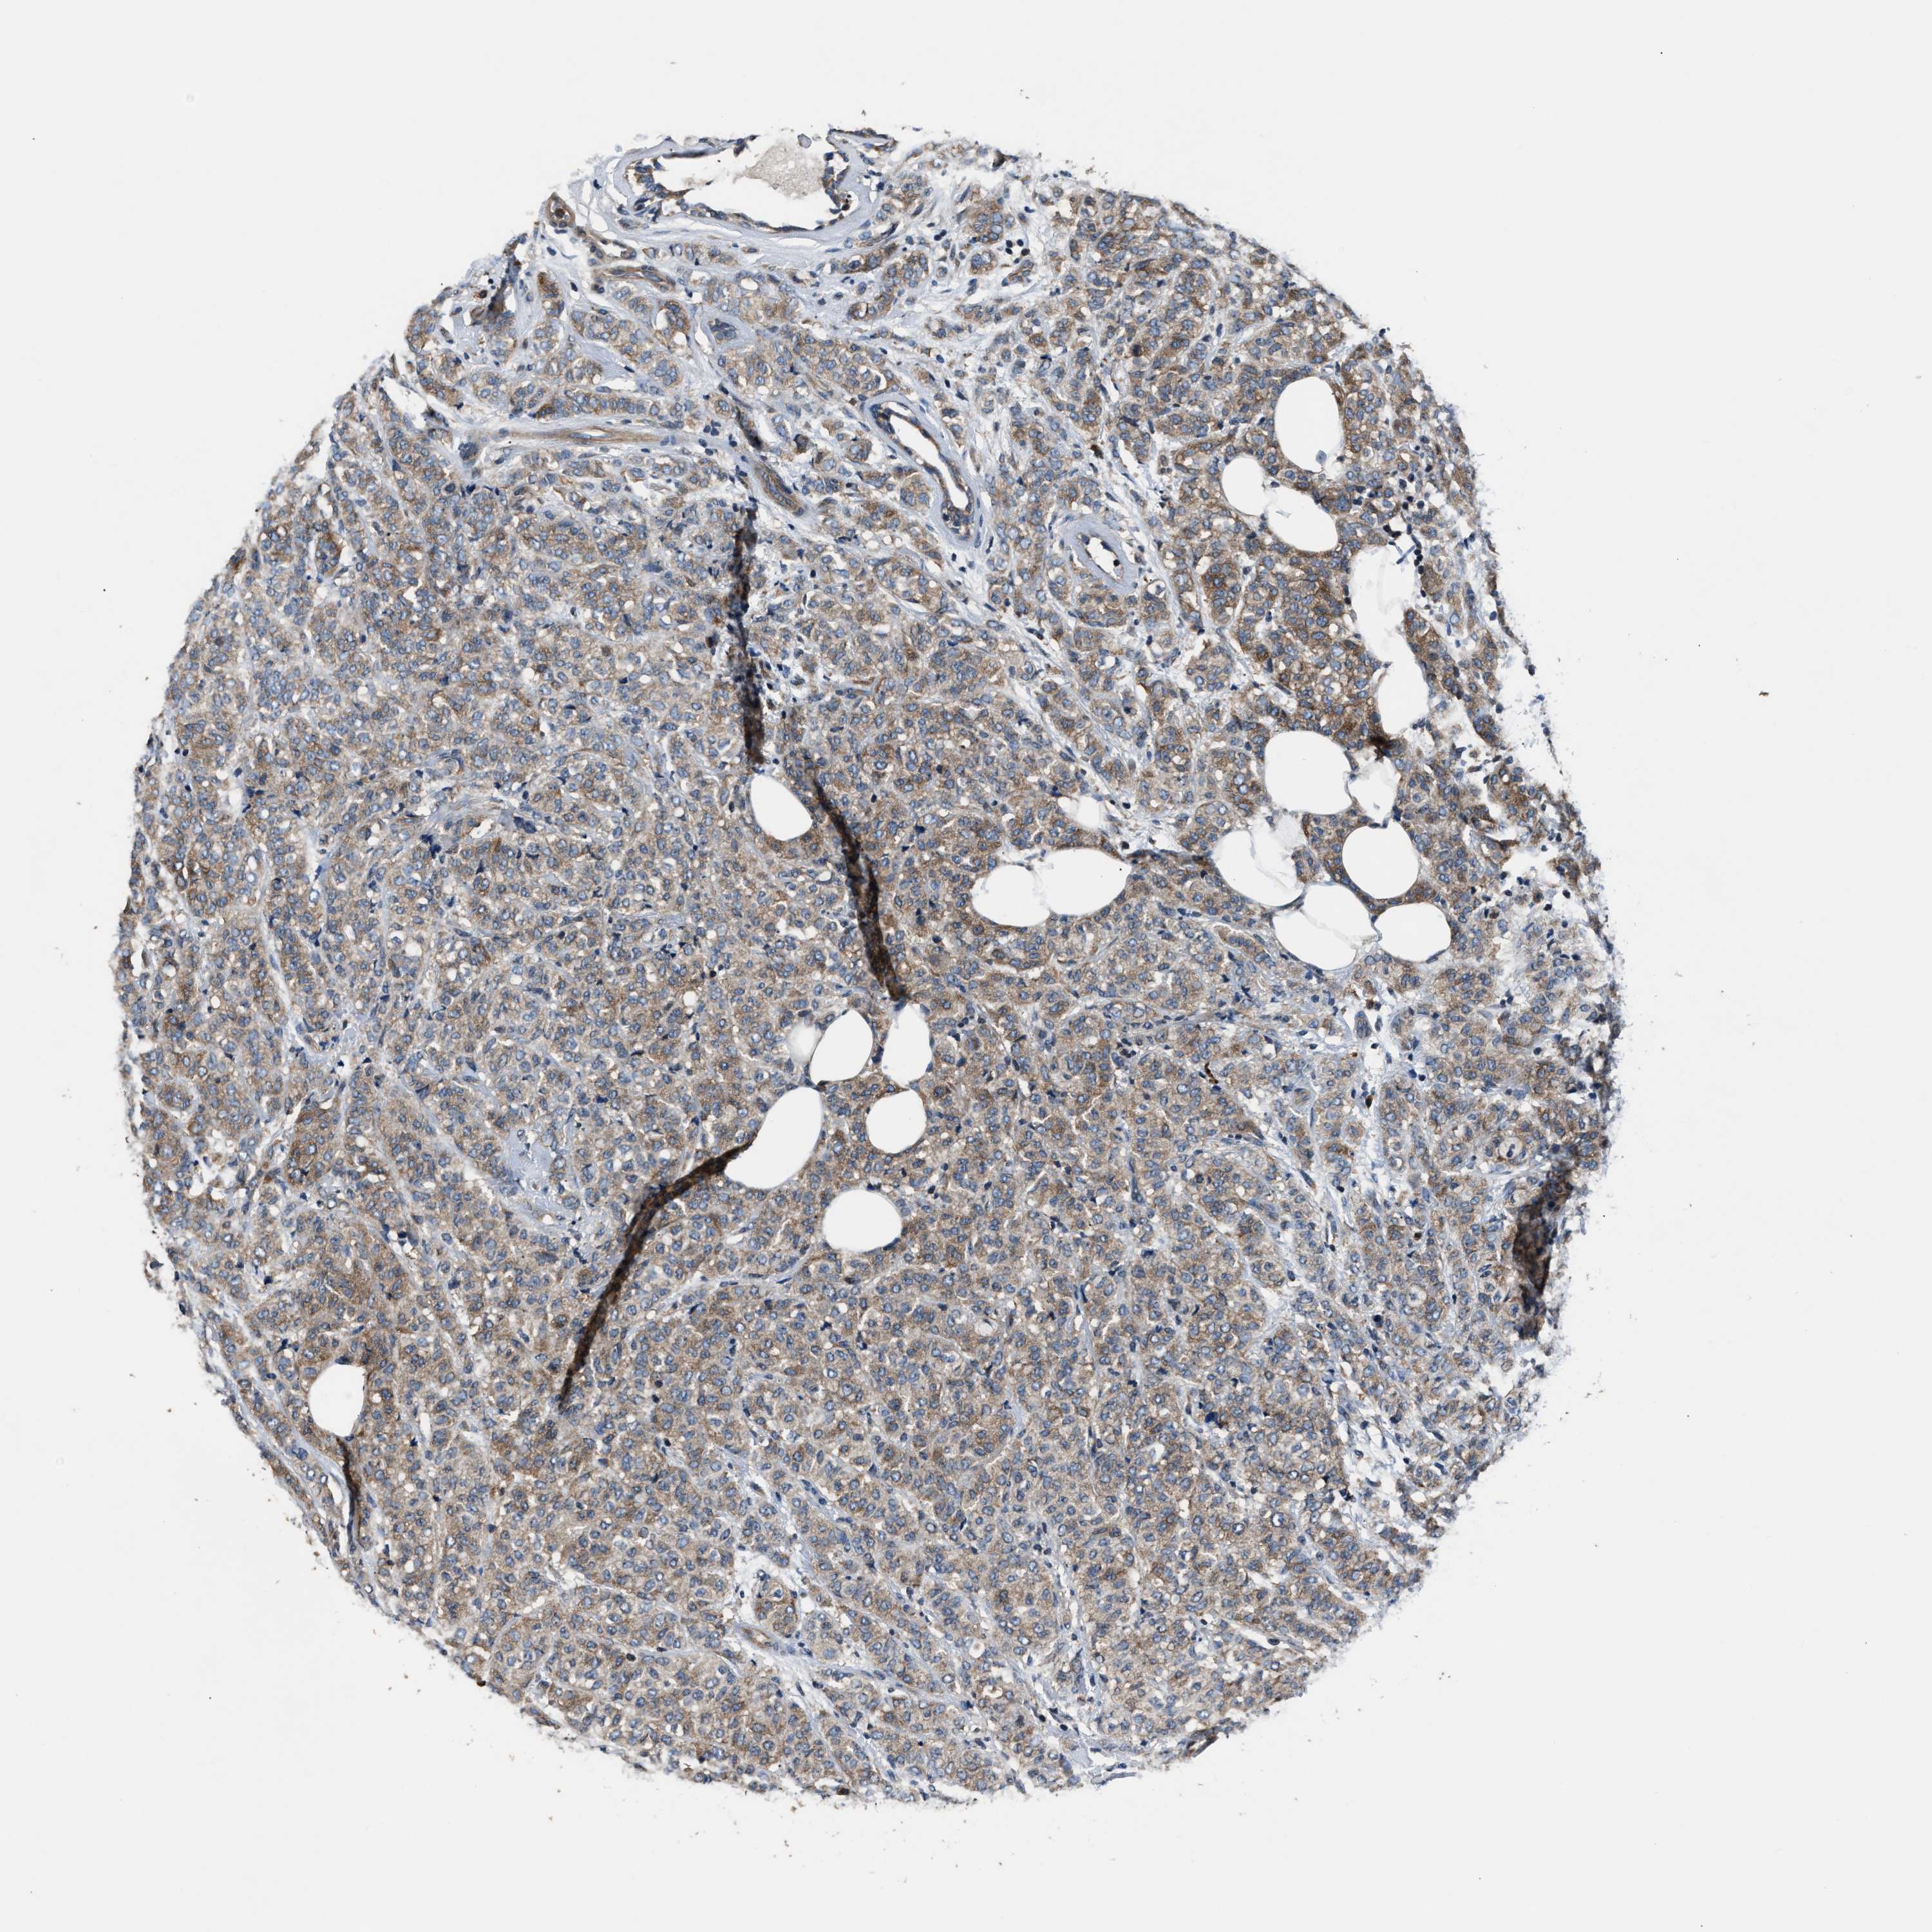

BRCA TCGA BRCA VALIDATION PROTEIN EXPRESSION

Breast cancer

Breast invasive carcinoma